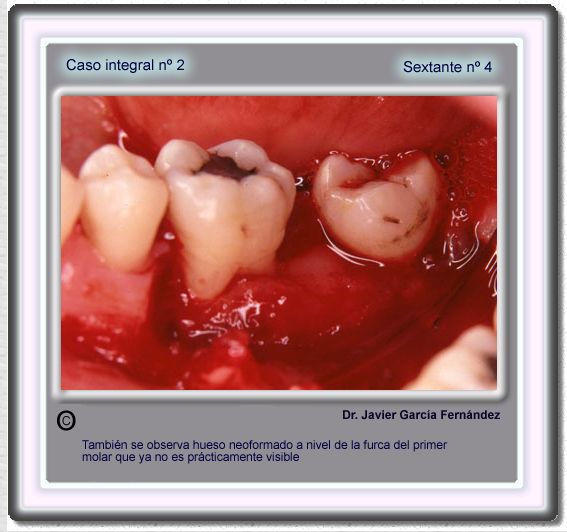

image 67